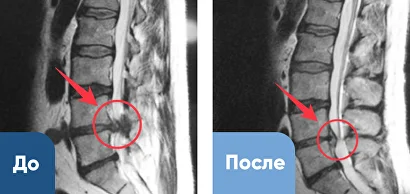

Лечение грыжи межпозвоночного диска

Уменьшение грыжи межпозвоночного диска и увеличение просвета позвоночного канала (спинного мозга). Результат за 2 месяца.